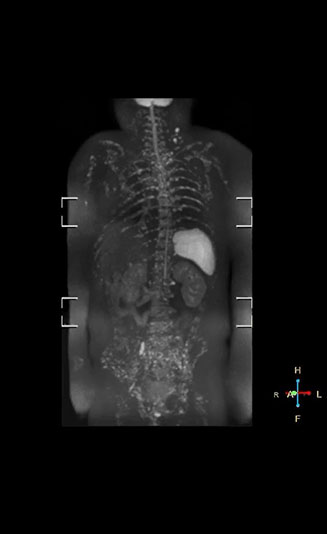

“With coronal DWIBS, we can perform a full whole body exam, including other sequences, within 30 min.”

Coronal DWIBS is faster and improves image quality

“Switching to coronal DWIBS – rather than axial – further shortens scan time,” says Mr. Naka. “Important is that a dS SENSE factor of 5 shortens exam time while high image quality can be maintained, thanks to Ingenia’s dStream architecture.” He adds that the coronal orientation also avoids artifacts that are specific to combining axial images.

“When we use a coronal DWIBS acquisition, we can perform a full whole body examination, including other required sequences, within 30 minutes,” he says.

“This is considerably faster than the previously used exam with axial whole body DWI, which took more than 45 minutes,” he notes. “A shorter exam is more patient-friendly and allows us to also use it on patients in poor health who would have difficulty tolerating a long exam. Limiting the exam time is also helpful for scheduling, because it fits in a normal single exam timeslot.”